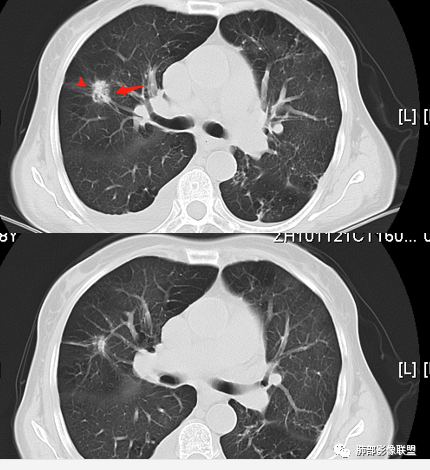

南边:   深分叶,胸膜凹陷在病灶凹陷处, 支气管近端截断

南边:   边界清楚GGO

南边:   毛刷南边:考虑恶性,进展,支持腺癌

1、老年女性,肺气肿背景,咯血多年,肿瘤标志物升高。    2、右肺上叶不规则结节影,八年后进行性增大为肿块,边缘深分叶、毛刺、棘状突起、胸膜牵拉,相应支气管壁增厚阻塞;周围局部见边界清楚的磨玻璃影;近胸壁侧见凹陷,整体呈外朝内生长。增强扫描呈不均匀明显强化,其内见坏死区,边界欠清。    3、右侧胸腔积液。纵隔见增大淋巴结。